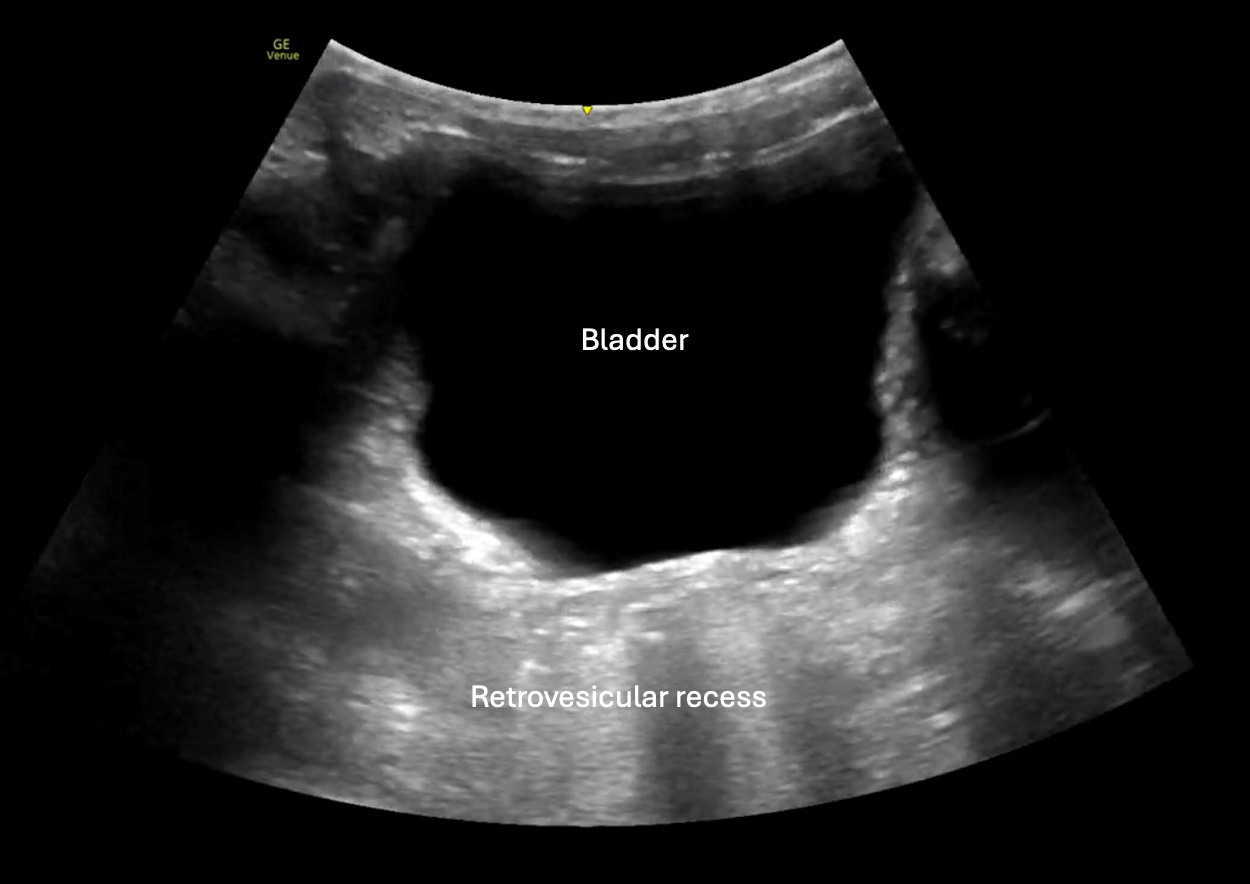

Suprapubic

The suprapubic view is obtained by placing either a phased array or curvilinear probe just superior to the pubic symphysis and angling inferiorly into the pelvis, with the probe marker oriented to the patient’s right for the transverse view. A second view should be acquired by rotating the probe 90 degrees (at this point the marker would be toward the patient’s head) for a longitudinal view. This dual-plane approach increases sensitivity and ensures proper evaluation of the rectovesical (in males) or rectouterine/pouch of Douglas (in females) spaces, where intraperitoneal fluid may first accumulate.

Among all FAST windows, the pelvic view is the most sensitive for detecting free intraperitoneal fluid in pediatric trauma, likely due to the relatively deep, midline location and the tendency of fluid to collect in gravity-dependent spaces.30 In contrast to adults, where Morison’s pouch is the earliest site of fluid accumulation, pediatric studies have shown that the pelvis is the first location to demonstrate free fluid in up to 66% to 85% of positive exams.28

Sonographic findings include anechoic fluid collecting in the posterior pelvis, outlining bladder margins, or pooling between the bladder and uterus in females. Small volumes can be missed if the bladder is decompressed, so it is ideal to scan when the bladder is partially distended.31 There is no established minimum fluid volume threshold for detection in pediatric patients, since values vary with body size, bladder filling, and probe resolution.

Limitations of this view include inadequate bladder filling, bowel gas artifact, and patient discomfort, which can affect image quality. Using a gentle technique and maintaining good probe contact with ample gel can improve visualization. As stated, a full bladder also may enhance diagnostic accuracy by serving as an acoustic window to the posterior pelvic space.29

Overall, the suprapubic view plays a critical role in pediatric trauma ultrasonography, especially when other FAST windows are equivocal or limited by anatomy or body habitus. Its inclusion is vital in detecting clinically significant hemoperitoneum, particularly in children with isolated lower abdominal injury or delayed presentation. (See Figure 4.)

Figure 4. Normal FAST Suprapubic View |

3-year-old male via curvilinear probe |

FAST: Focused Assessment with Sonography for Trauma Image courtesy of: Matthew D. Holmes, MD. |